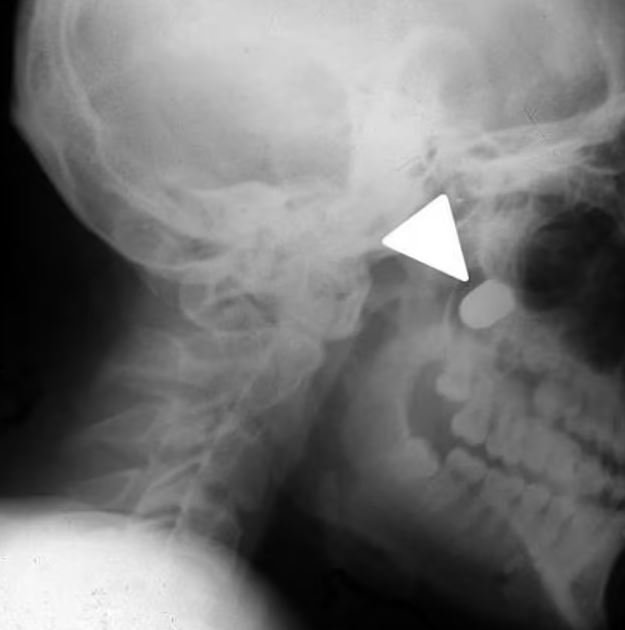

Adı açıklanmayan 16 yaşındaki sivil kurban, Sovyet yapımı bir tabancayla ensesinden vuruldu. Doktorlar, kurşun yarasına bakarak, çocuğun Makarov tabancasıyla yaklaşık 15 cm'den vurulduğunu tahmin ettiklerini belirttiler.

9 mm'lik merminin boyna girdiğini, omurganın ucunu sıyırdığını ve üst çeneye saplandığını gördü. Genç, Ukrayna'nın merkezindeki Vinnytsia şehrinde bir hastaneye götürüldü. Çocuğun yüzünün sol tarafı ve boynu şiş; omuriliğindeki hasar nedeniyle ağzı tam olarak açılamıyor ve sol kolunu da kaldıramıyordu.

Ameliyat sırasında doktorlar çenesinin alt kısmından bir kesi yaparak bölgedeki yumuşak dokuyu parçalara ayırdı ve mermi kabuğunu kafatasından çıkardı.

Daha sonra bölgeyi tedavi edip yarayı diktiler. Çocuk, ameliyattan dokuz gün sonra hastaneden taburcu edildi. Ve şaşırtıcı bir şekilde tamamen iyileşti.